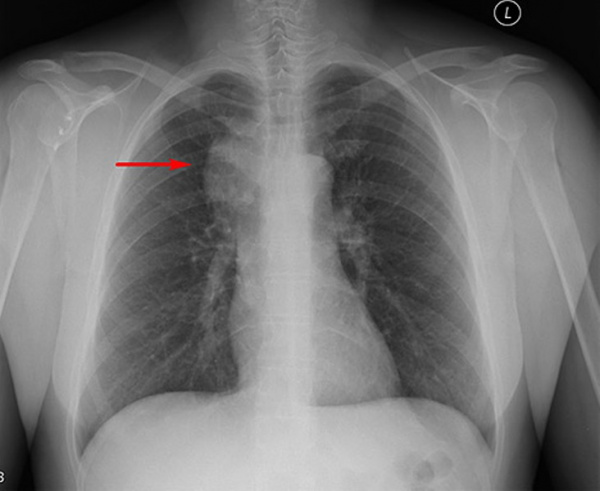

(Слева) КТ с КУ, аксиальная проекция у пациента с единичным пальпируемым образованием на шее, которое равномерно накапливает контраст. Визуализируется крупный лимфоузел, умеренно накапливающий контраст, рядом расположены сосуды. Был поставлен диагноз унифокальной гиалиново-васкулярной формы болезни Кастлемана. Полное излечение достигнуто путем удаления лимфоузла.

(Справа) МРТ Т1ВИ FS с КУ, другой пациент с гиалиново-васкулярной болезнью Кастлемана. Узлы правой яремной цепи однородно накапливают контраст. Узел, расположенный кзади, достигает больших размеров. Признаков воспаления или внекапсулярного распространения нет. (Слева) КТ с КУ, коронарная реконструкция. Крупный, однородный узел В правой яремной цепи, накапливающий контрастное вещество. Также видны мелкие узлы уровня IV и противоположной яремной цепи, которые накапливают контраст менее интенсивно.

• О диагнозе следует думать при обнаружении образования, расположенного вдоль яремной цепи, которое умеренно или интенсивно накапливает контраст; рядом обычно имеется развитая сосудистая сеть

• КТ с контрастированием: центральный рубец, не накапливающий контраст; встречается редко

• МРТ Т2: описывают гипоинтенсивные полосы; встречается редко

• При УЗИ имеет гипоэхогенную структуру с усиленным периферическим кровотоком